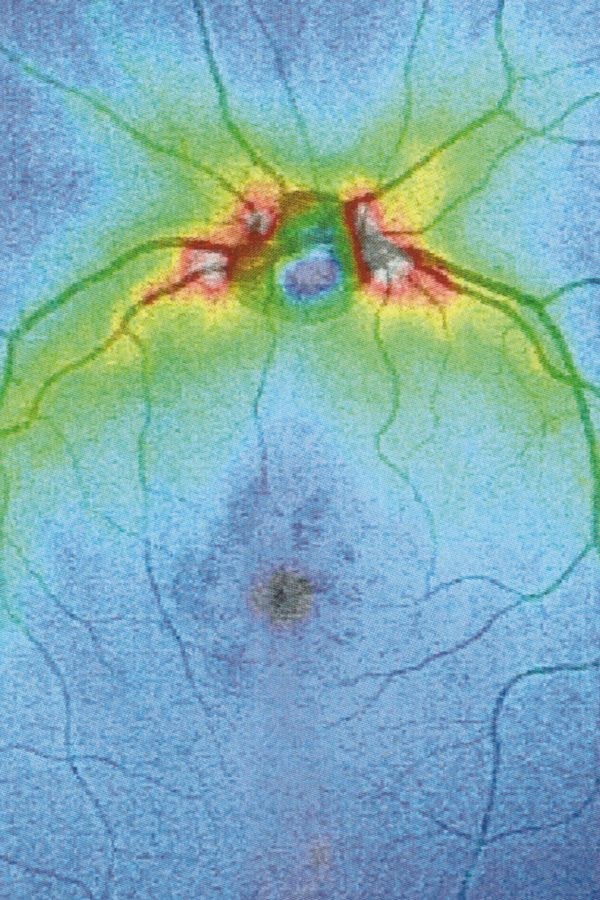

Following a terrifying experience with a too high dose of LSD when I was 16, something has changed in the way I observe visible reality. A hypertrophic screen materialized between me and the world, a scar of opacity. The fear of hallucination teaches a new language, so that every meaning remains trapped in a net and only the signifier filters through its meshes. No shadow, only empty light. Anguish arrests every retinal projection on that screen. Every perception is immobilized to be inspected for a hallucinatory return, it is reified, detached from its real referent, reduced to representation, incapable of referring to something outside of it. And behind (or in front) of it, the eyes have stolen consistency from reality. The body only appears occasionally, at the edges of the mind, when we engage in apperception. And yet I feel the tinkling of a gear that draws my attention inside my eye. I reflect on myself, I look back and from the inside. Once vision is situated in the empirical immediacy of the body, it belongs to time, to flow, to the end.

Collirio (Eye wash) is the attempt to demonstrate the non-absoluteness of visual experience, its nature as a situated, and yet, ambiguous act. It is the path that has allowed me to understand how my fears do not have roots in an unknowable place. The eye is not an unfathomable globe.

When we learn to speak, we are immersed in systems of discourse that pre-exist us and will survive us. So it is with seeing. Between us who observe and the world, there is inserted the set of discourses that constitute visuality and that make it different from vision. Between the retina and the world, a screen of signs is inserted, a screen composed of all the multiple discourses on vision constructed in the arena of collectivity. This screen casts a shadow, Jacques Lacan calls it “scotoma”, “a stain”. Because when we look through the screen, what we see is trapped in a net and can only project towards us the shadow itself of its signifier, its meaning. In the visual field, something cuts, cuts through, parallel to the pupil. It is the fabric of practices, habits, languages, all linked to the reality of representations, with which the meaning of what we see is casted as a shadow.